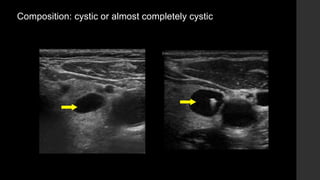

Composition: cystic or almost completely cystic